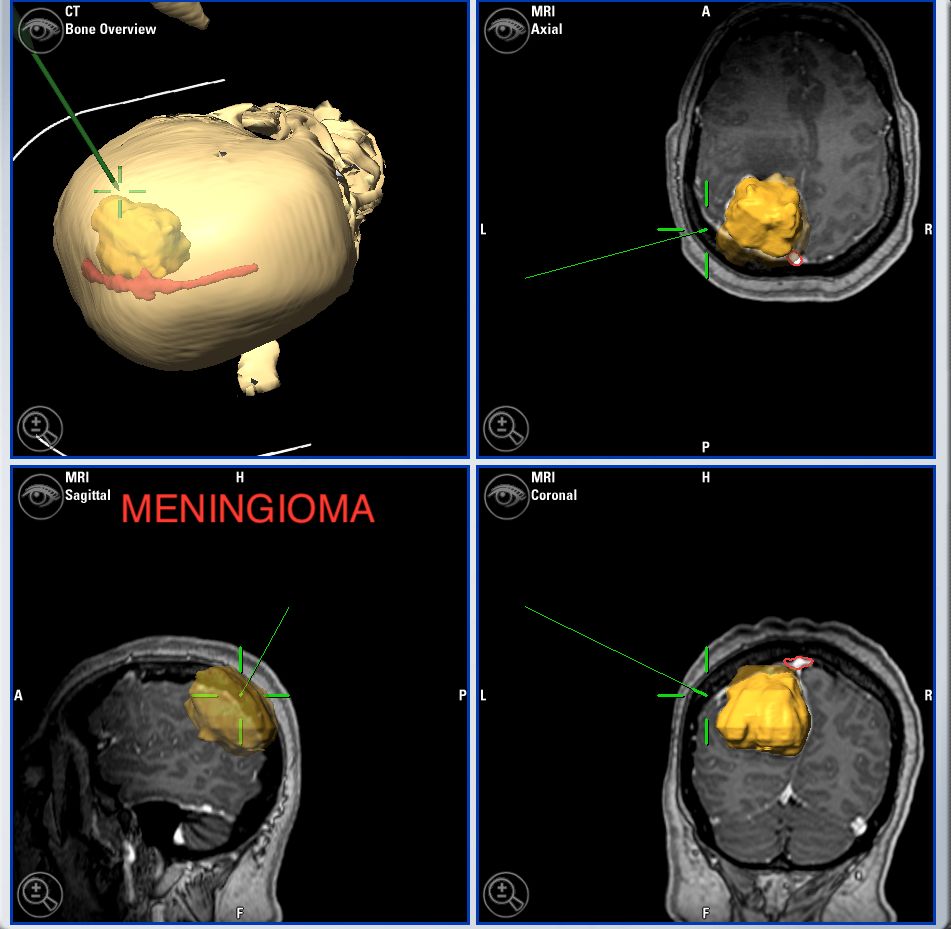

Meningiomas